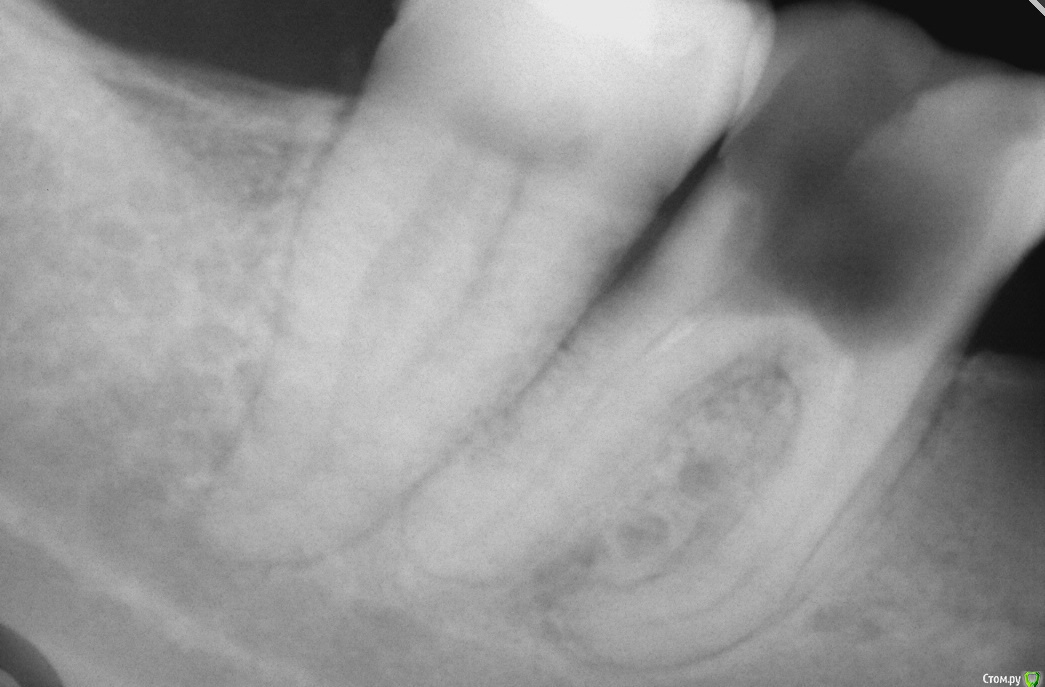

simpsons Опубликовано 7 декабря, 2016 Поделиться Опубликовано 7 декабря, 2016 Пациентка обратилась по поводу лечения 46. Ранее зуб был лечен 3 месяца назад в другой клинике. Зуб открыт,не беспокоит. Интересно мнение коллег. Удалять или лечить? Ссылка на комментарий

simpsons Опубликовано 7 декабря, 2016 Автор Поделиться Опубликовано 7 декабря, 2016 добавлю.Кариес в полости зуба снимался пластами. Рот открывается слабо. Ссылка на комментарий

St. Опубликовано 7 декабря, 2016 Поделиться Опубликовано 7 декабря, 2016 (изменено) Если твердых тканей достаточно по стенкам и по фуркации тоже( по снимку там тонковато...) то эндо и коронка.По поводу доступа - решать Вам, сможете это адекватно сделать или стоит отправить куда-то. Но тут еще нужно учитывать хочет ли это пациент и готов ли на это финансово. Если месяц ходит с открытым недолеченым зубом, то в этом есть сомнения. Изменено 7 декабря, 2016 пользователем St. 2 Ссылка на комментарий

simpsons Опубликовано 7 декабря, 2016 Автор Поделиться Опубликовано 7 декабря, 2016 Спасибо.Стенки очень тонкие Ссылка на комментарий

Kolchanov Опубликовано 7 декабря, 2016 Поделиться Опубликовано 7 декабря, 2016 Это снимок после некрэктомии? Если так, то я бы предложил покрутиться. Вполне годный зуб. 1 Ссылка на комментарий